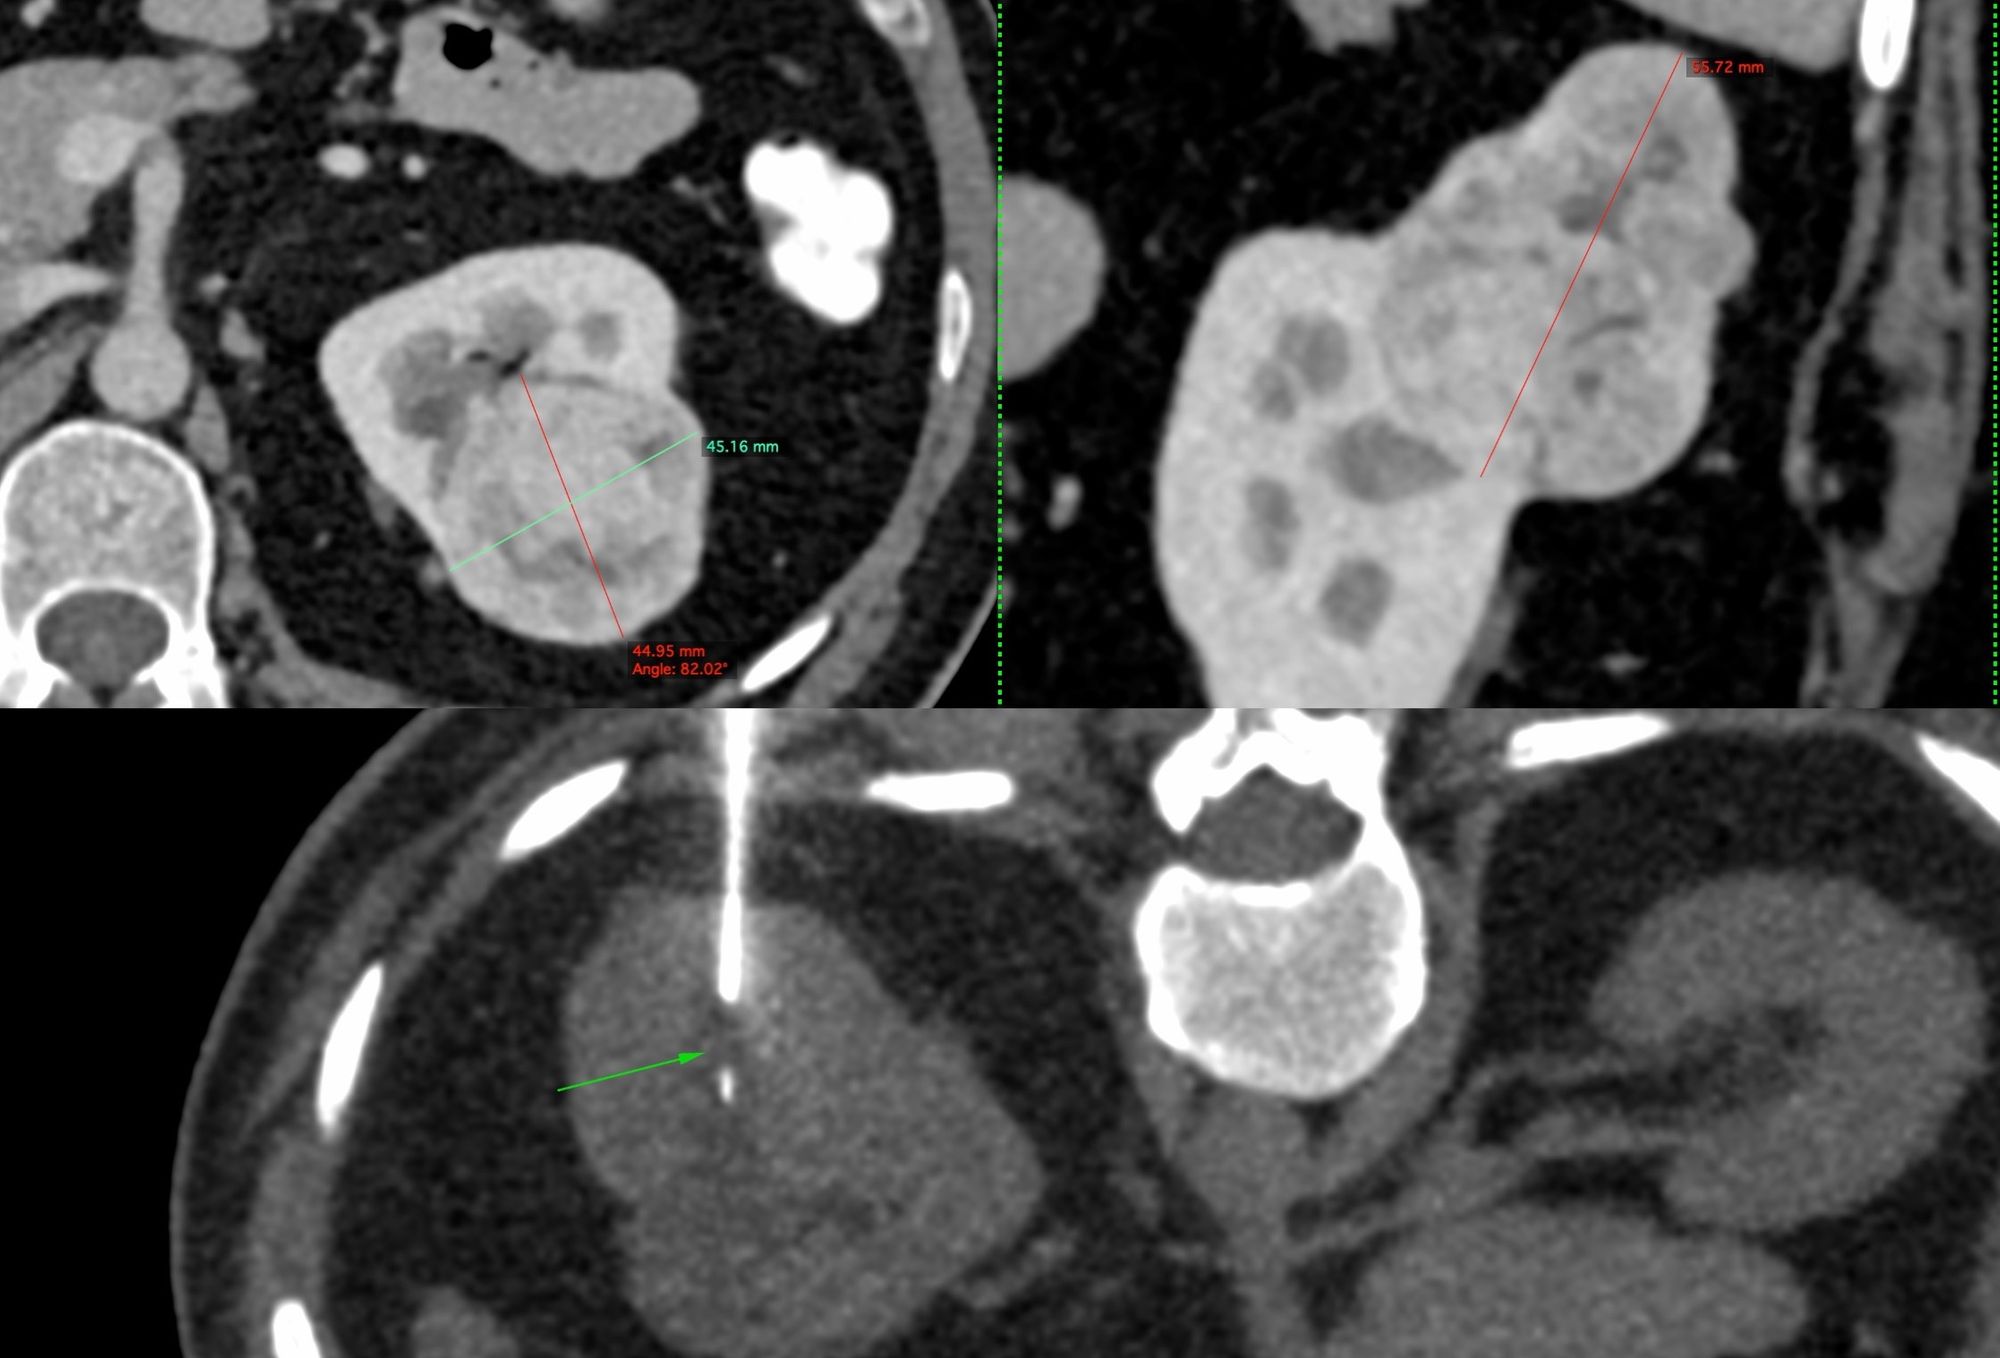

Case 19: 5.6 cm Renal Mass Biopsy